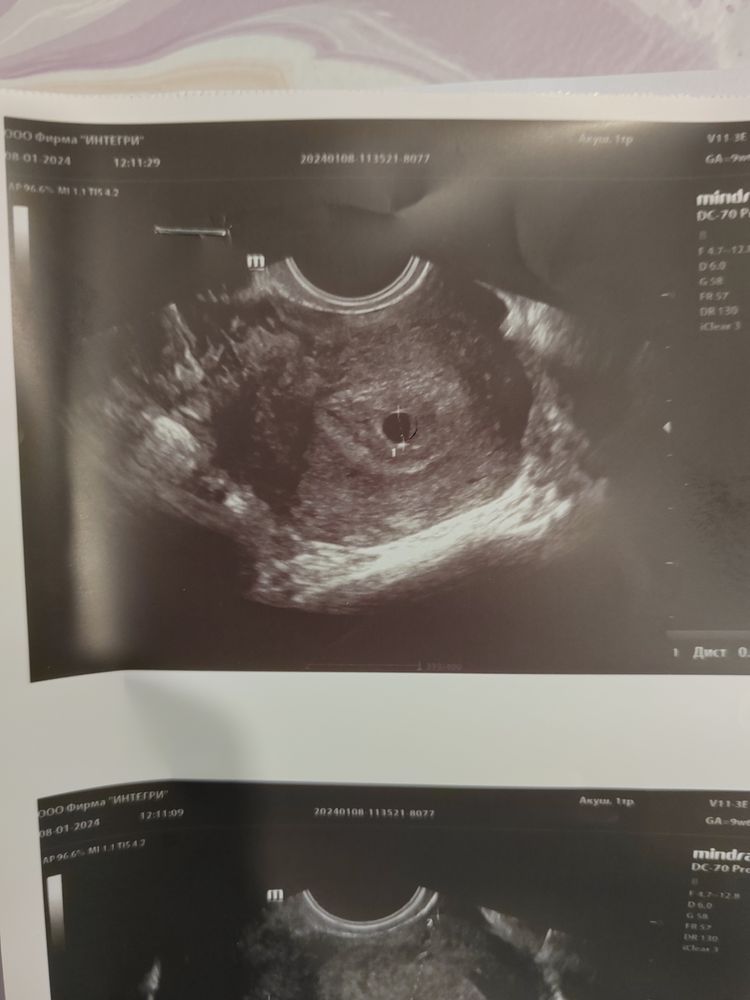

Мажущие выделения, не совпадает срок Б

Мама мальчика (2 года) Нижний Новгород

Если за столько дней плодное яйцо выросло на два мм, то дела явно плохи. С другой стороны первое узи странное